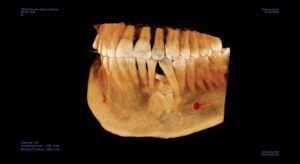

طلب منى اشعة بانوراما عادية علي الفكين و عملتها و تم عرضها علية فعاد و طلب مقطعية للتأكد من شيء موجود تحت الناب الايسر بالفك السفلي و بالفعل عملت المقطعية وتم عرضها علية

وقالي هنتابعها هى حاجة عندك من سنين طويلة يمكن اكتر من ٢٠ سنة و موجودة في اشعات البانوراما القديمة اللي كنت بتعرضها علي دكتور شريف المفتي في ٢٠١١ و ٢٠١٢ رحمة الله علية هى اسمها compound odontoma و حاجة حميدة تماما و لا خوف منها و ممكن تعيش بيها لكن هنتابع حجمها بالمقطعية كل ٦ شهور و متقلقش منها .

قولت اعمل اشعة بانوراما مع نفسي كدا اطمن علي المشكلة.. لقيت الحجم شكلو متغير عن اللي فاتو بتوع ٢٠١٨ و ٢٠١١

و٢٠١٢ بعتها لدكتور محمد المفتي واتس واتصلت علية .. قالي مالك مال صوتك مخنوق !

قولتلة انا ملاحظ تغيير قالي نعمل مقطعية قولتلة فين قالي مضطر تنزل القاهرة كدا

قولتلة طبعا قالي انا هكون موجود هناك غدا بكلية طب الأسنان تعالي و هنعمل مقطعية عندنا و بالفعل روحت قالي اسمع البانوراما دى بايظة و مش هيطلع اي تغير قولتلو لا يا دكتور انا ملاحظ الاشعة و الفرق قالي ماشي يا فندم بينا المقطعية!

و من قلقي كل شوية اتصل علية و الراجل يرد و يشرح و يشرح و انا منتظر المقطعية لحد ما عملت المقطعية من يومين و تركت ال cd للدكتور محمد المفتي لان وجدته في اجتماع مع رئيس جامعة النهضة بني سويف

و بعد عرض ال cd قومت بالاتصال علية قالي مافيش اي تغير يا نادر زى ماهي و مافيش حاجة تخوفني.